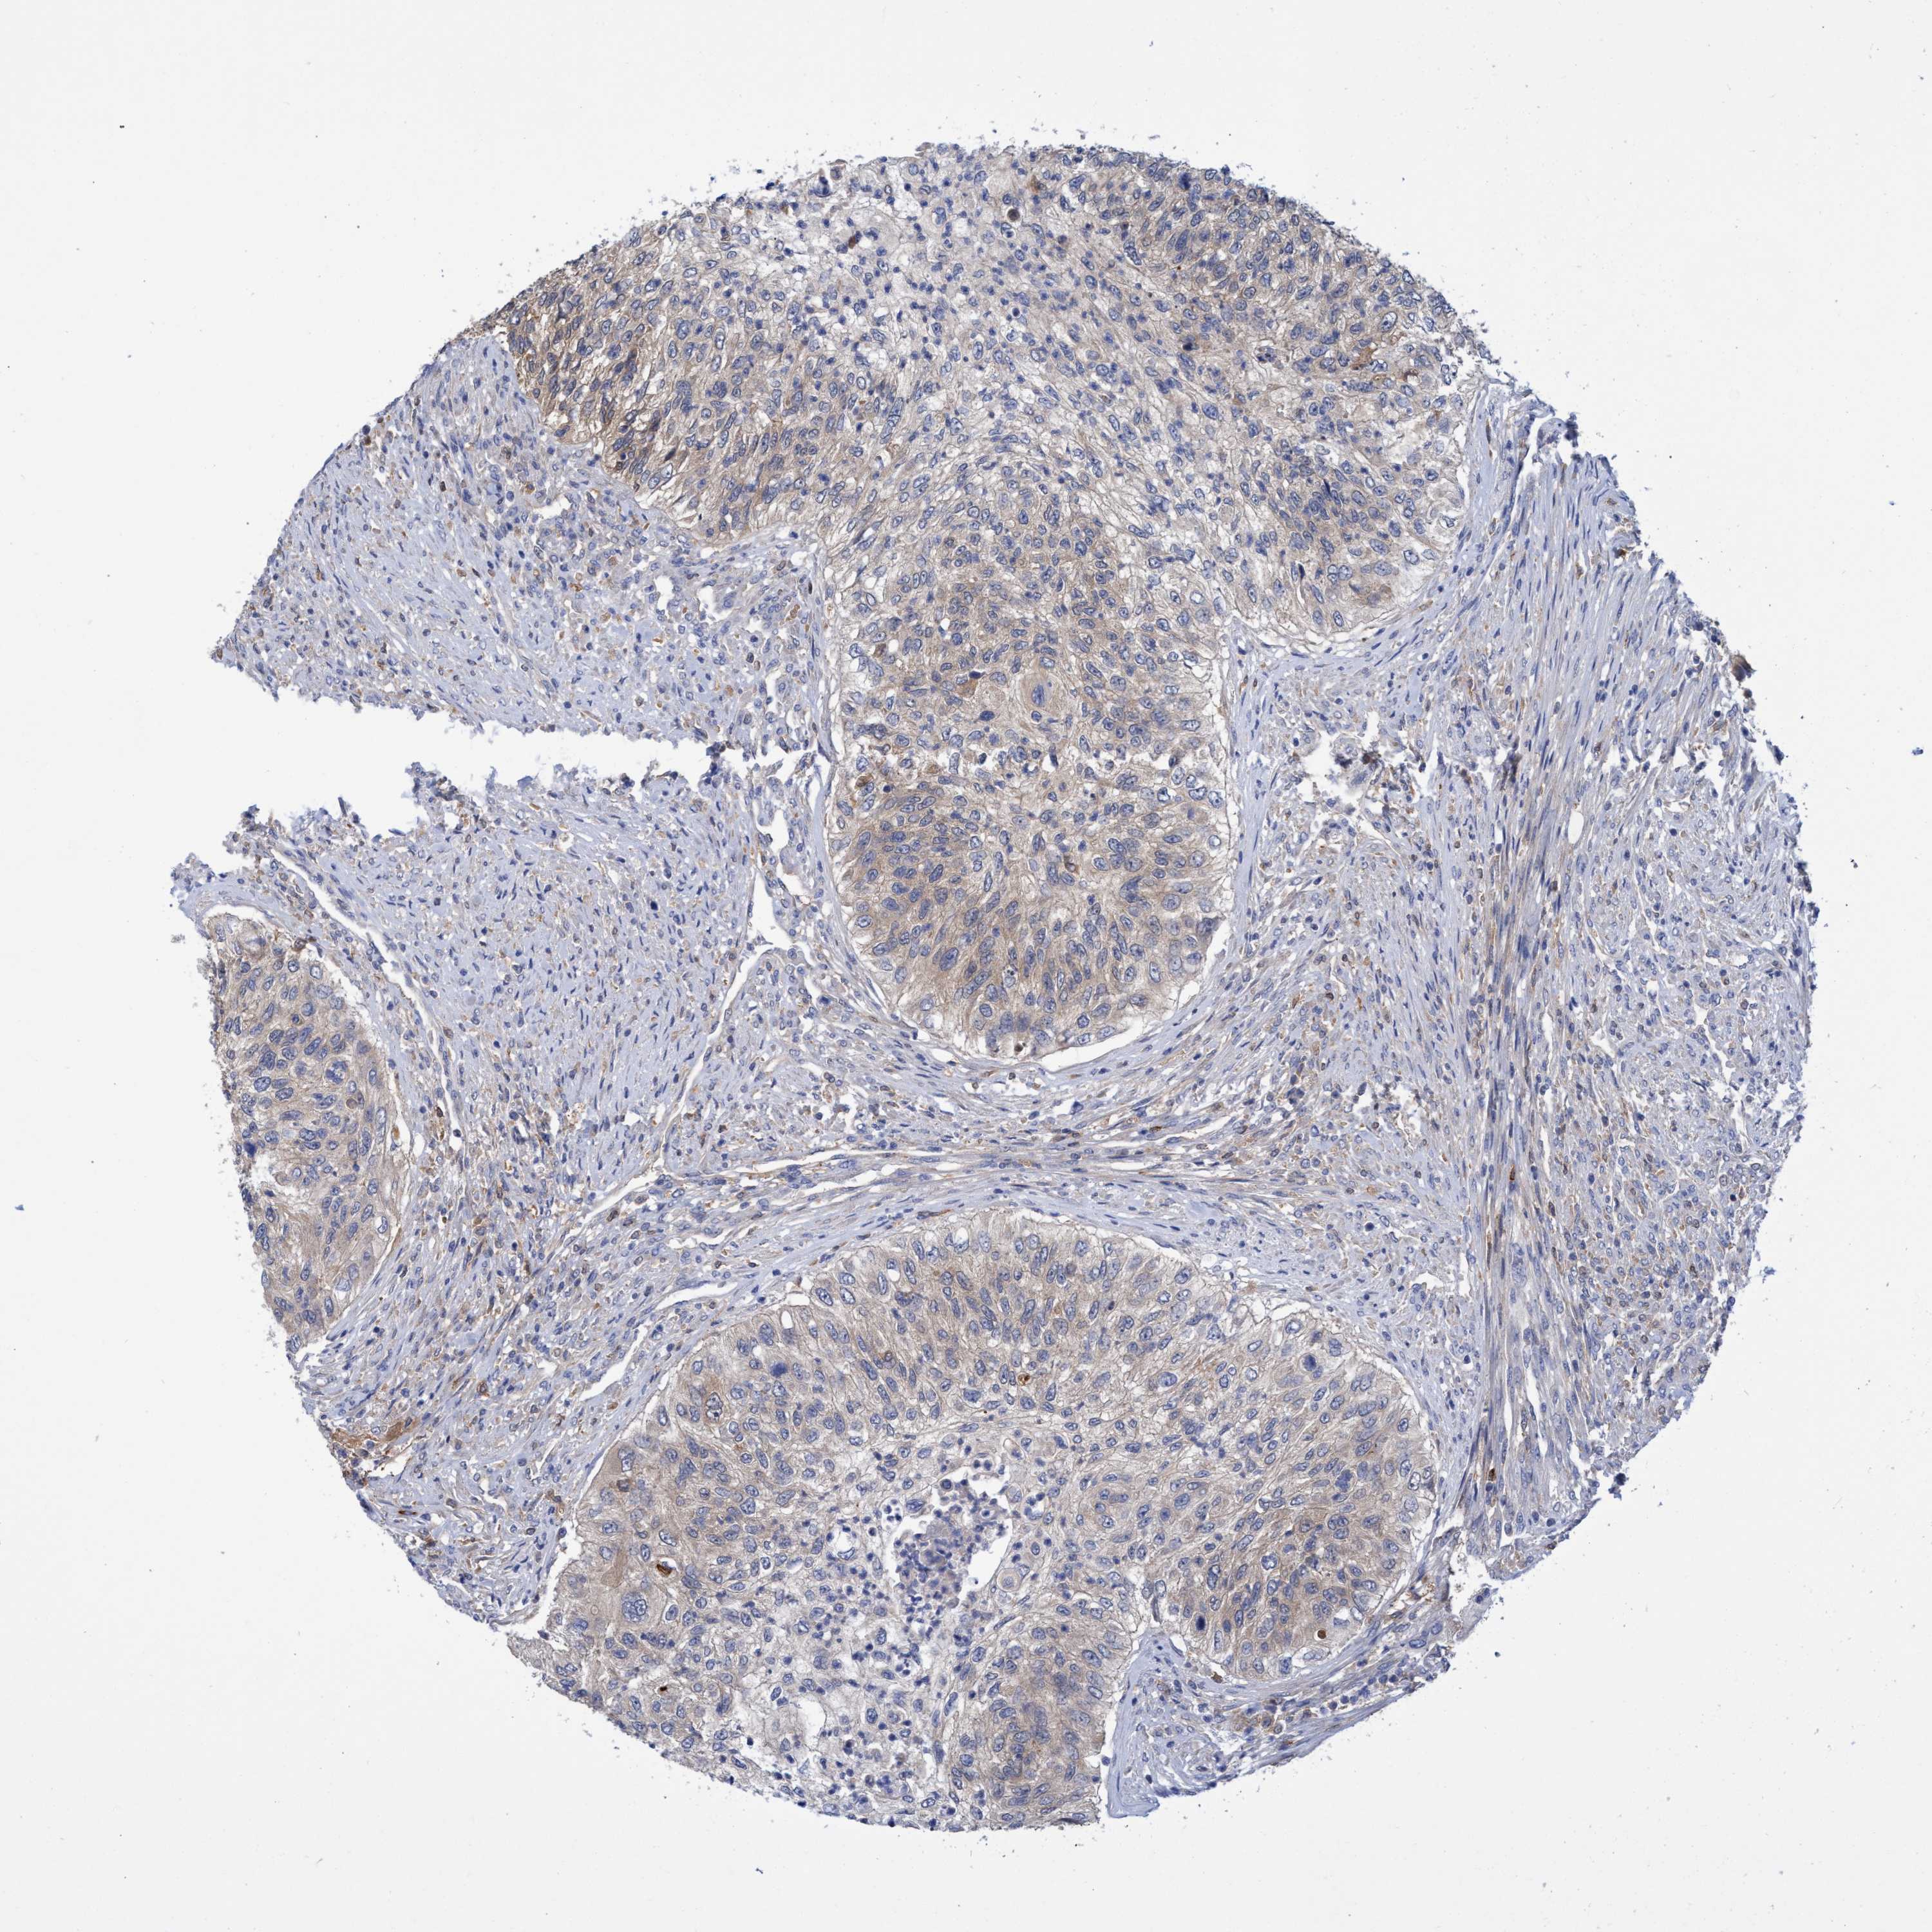

UROTHELIAL CANCER - Protein expressioni

A mouse-over function shows sample information and annotation data. Click on an image to view it in a full screen mode. Samples can be filtered based on level of antibody staining by selecting one or several of the following categories: high, medium, low and not detected. The assay and annotation is described here.

Note that samples used for immunohistochemistry by the Human Protein Atlas do not correspond to samples in the TCGA dataset.

Antibody stainingi

Antibody staining in the annotated cell types in the current human tissue is reported as not detected, low, medium, or high, based on conventional immunohistochemistry profiling in selected tissues. This score is based on the combination of the staining intensity and fraction of stained cells.

Each image is clickable and will lead to virtual microscopy that enables deeper exploration of all samples and also displays staining intensity scores, fraction scores and subcellular localization as well as patient and tissue information for each sample.

Antibody HPA023204

Antibody HPA027776

Urothelial carcinoma, Low grade

Urothelial carcinoma, High grade